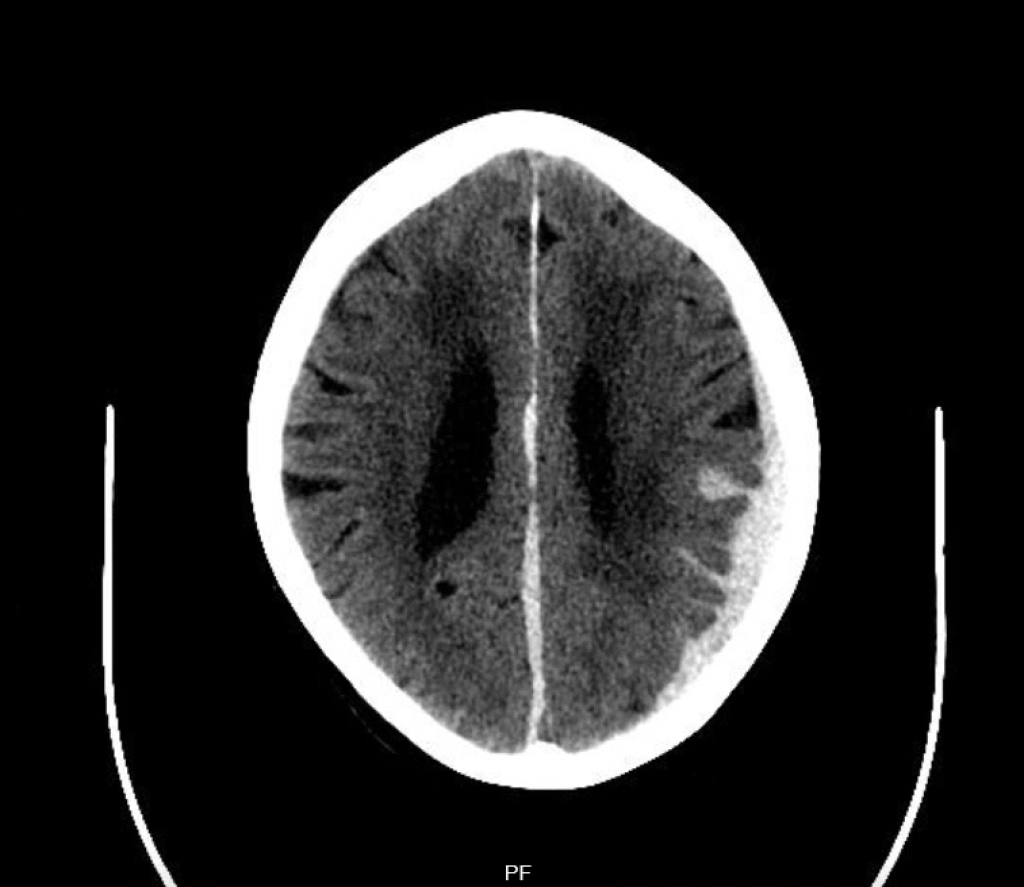

Subduralhämatom

Subduralhämatome können chronisch im Rahmen einer Sickerblutung oder akut – dann oft bei bestehender Antikoagulation – durch den Einriss von Brückenvenen entstehen. Da das Gehirn langsame Druckänderungen und Masseverschiebungen viel besser toleriert als akute können chronische Subduralhämatome viel größere Ausdehnungen erreichen, bevor sie überhaupt Symptome verursachen.

Während es bei akuten Subduralhämatomen relativ klare OP-Indikationen für eine Bohrlochtrepanation gibt (Hämatomdurchmesser > 10 mm, Mittellinien-Verlagerung > 5 mm, GCS < 9 Punkte, GCS-Abfall um 2 Punkte, Anisocorie und Hirndruck > 20 mmHg), ist das bei chronischen Subduralhämatomen anders. Hier kommt es zu – sich oft im Verlauf auch selbst resorbierenden – Sickerblutungen, eine relative OP-Indikation besteht bei einem symptomatischen Subduralhämatom und einer bildmorphologischen Hirnparenchym-Kompression. Hier müssen aber immer Nutzen und OP-Risiko bei den oft hochaltrigen, multimorbiden und in der Regel hochgradig delirgefährdeten Patienten abgewogen werden, auch weil das Rezidivrisiko bei chronischen Subduralhämatomen mit ca. 30% sehr hoch ist. Mit der Embolisation der A. meningea media steht zudem – momentan (auch auf Grund der fehlenden aktuellen Leitlinie) nur in Studien durchführbare – interventionelle Behandlungsmöglichkeit zur Verfügung. Idee der Embolisation ist es, das oft sehr fragile Kapillargeflecht, was in die Brückenvenen mündet zu veröden.